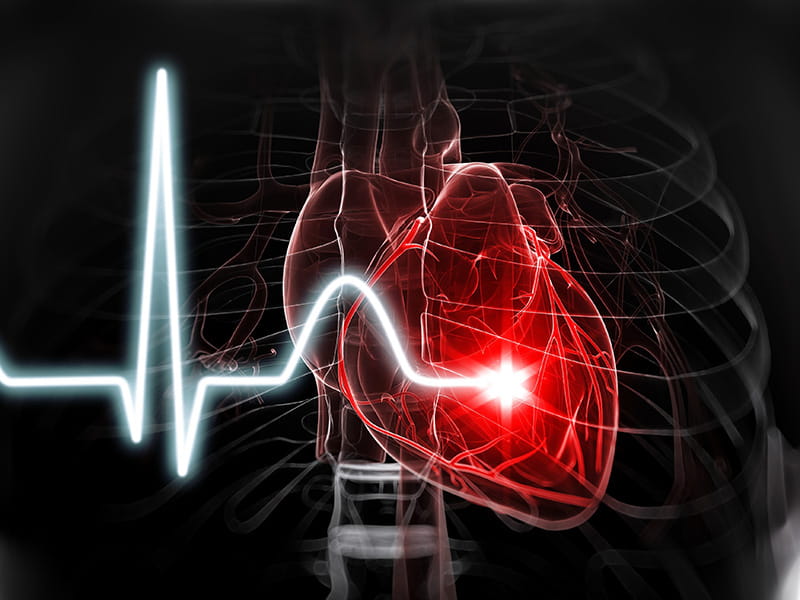

An updated guide to the latest research on heart disease and stroke is filled with important data for experts fighting these debilitating problems.

But to those responsible for the guide, “2026 Heart disease and stroke statistics: A report of US and global data from the American Heart Association” is about more than lines on charts.

Heart disease is by far the leading cause of death in the United States

Heart disease remains the leading cause of death in the US, while stroke has moved up to No. 4, replacing COVID-19, which fell to No. 10, according to the update.

Combined, heart disease and stroke accounted for more than a quarter of all deaths in the United States in 2023, the most current year for which data is available.

Cardiovascular disease, including all types of heart disease and stroke, claims more lives in the United States each year than the No. 2 and No. 3 causes—cancer and accidents—combined. Someone died from cardiovascular disease every 34 seconds on average in 2023.